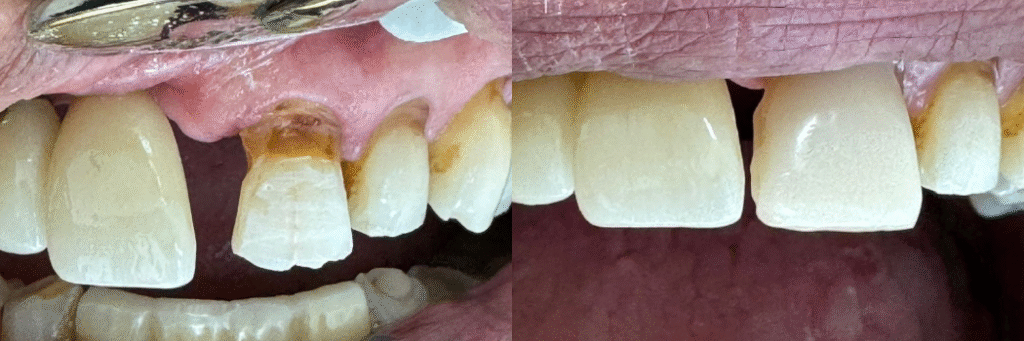

Carilla en diente desvitalizado